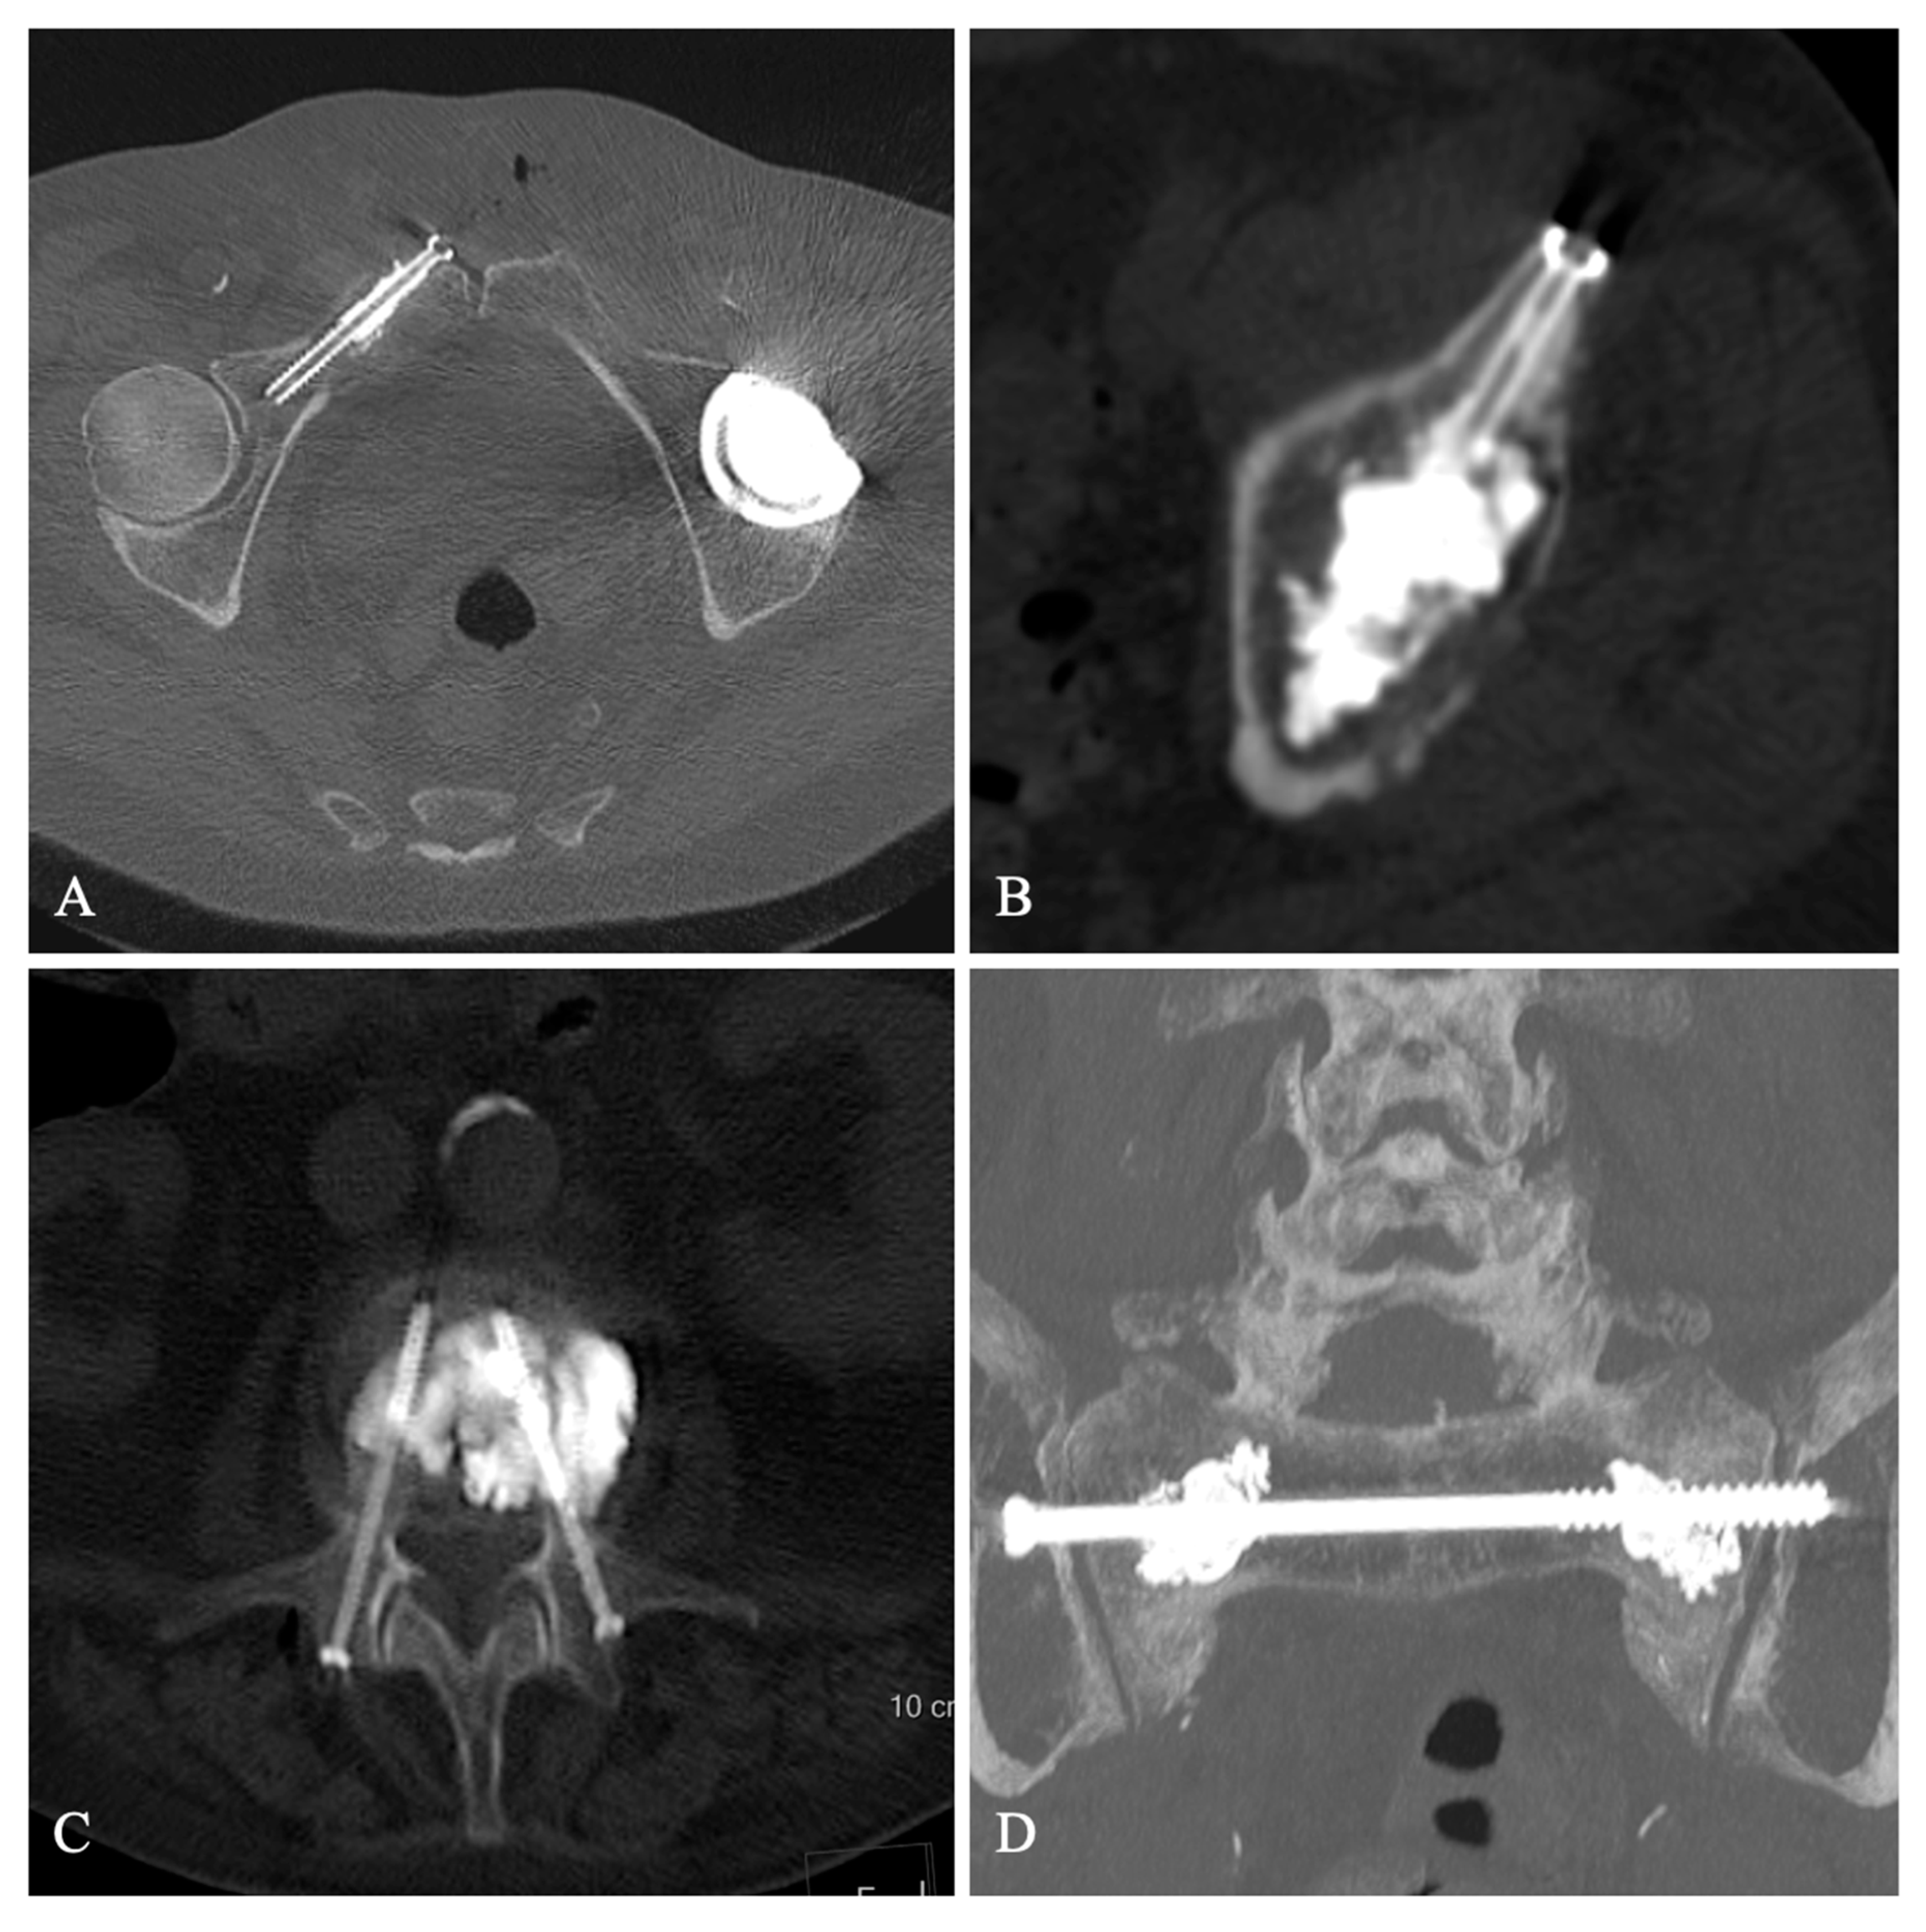

3. Results

Figure 1. Screw fixation of a right iliopubic branch metastasis (A), Screw fixation of a myeloma lesion of the left acetabulum (B), Bipedicular screw fixation with cementoplasty of an osteoporotic vertebral fracture with osteonecrosis (C), Transiliac screwing with sacroplasty of an insufficiency sacral fracture (D).